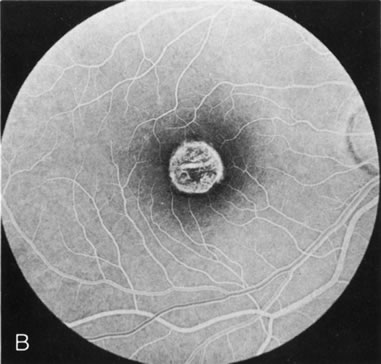

The intact solid yellow egg yolk lesion in Best's vitelliform macular dystrophy (BVMD) typically shows hypofluorescence on FA due to blockage of the underlying choroidal fluorescence with the overlying retinal vasculature visible (Fig. 10A and, B). This finding places the lesion in front of the choroid, possibly within the RPE, but probably not within the neurosensory retina. There is no histopathology of the intact lesion to confirm this.

Fig. 10. Best's vitelliform macular dystrophy. The most characteristic angiographic finding in the solid yellow egg-yolk stage is blocked hypofluorescence (A, B). A morphologically mimicking lesion (pseudovitelliform degeneration) may be the result of leakage from the underlying choroid (C–E).

There are several acquired macular degenerations of different etiologies that have a macular lesion similar to the vitelliform stage of BVMD. FA may be helpful in identifying these cases of pseudovitelliform degeneration by showing leakage from the retinal capillaries or through the RPE and late staining of the lesions (Fig. 10CE). However, the electro-oculogram remains the most discriminating test because it is always abnormal in BVMD and usually normal in pseudovitelliform macular degeneration.